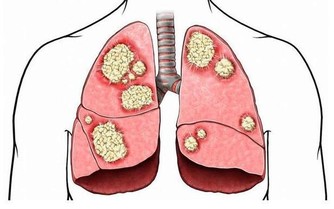

有時候落枕是大問題的症狀,和椎間盤突出或神經受壓差不多。

這種傷害可能自己康復不了,要求醫來確認自己是否需要醫治。